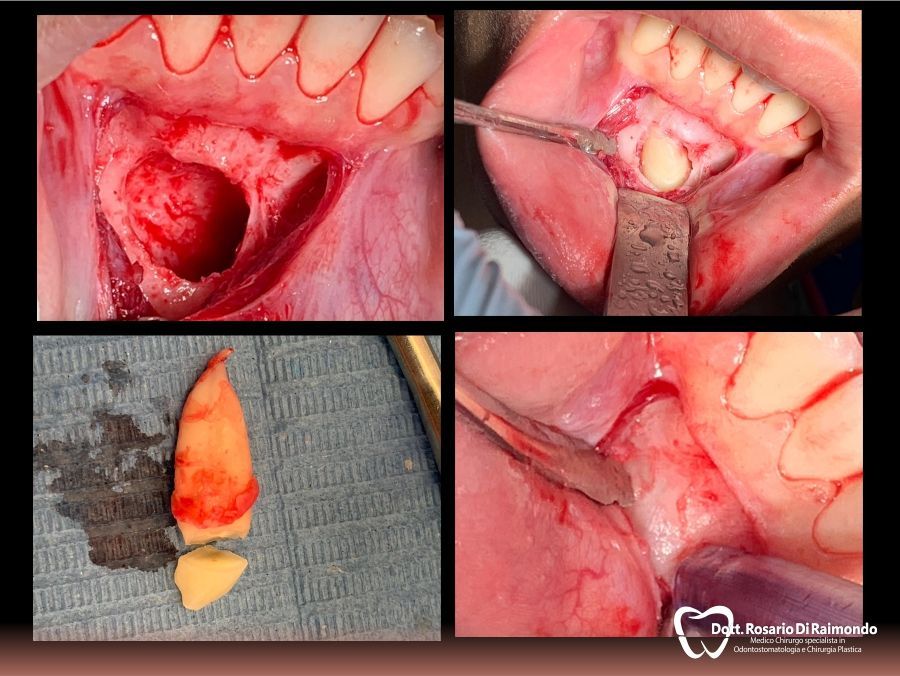

Cisti

La cisti è una formazione patologica che presenta una forma generalmente sferica ed ha la tendenza ad un lento accrescimento asintomatico a spese dei tessuti circostanti.

L'aumento di volume di una cisti può portare al riassorbimento delle radici di denti contigui e dei tessuti ossei che la contengono. In altre occasioni si può verificare la dislocazione degli elementi dentali adiacenti.

La posizione e la velocità di crescita di una cisti sono due dei fattori che il dentista prende in considerazione nel decidere se procedere alla rimozione chirurgica della stessa o monitorarla nel tempo tramite controlli clinici e radiografici periodici.

Casi Trattati

Di seguito riportiamo alcune fotografie di casi esplicativi di Chirurgia Orale.